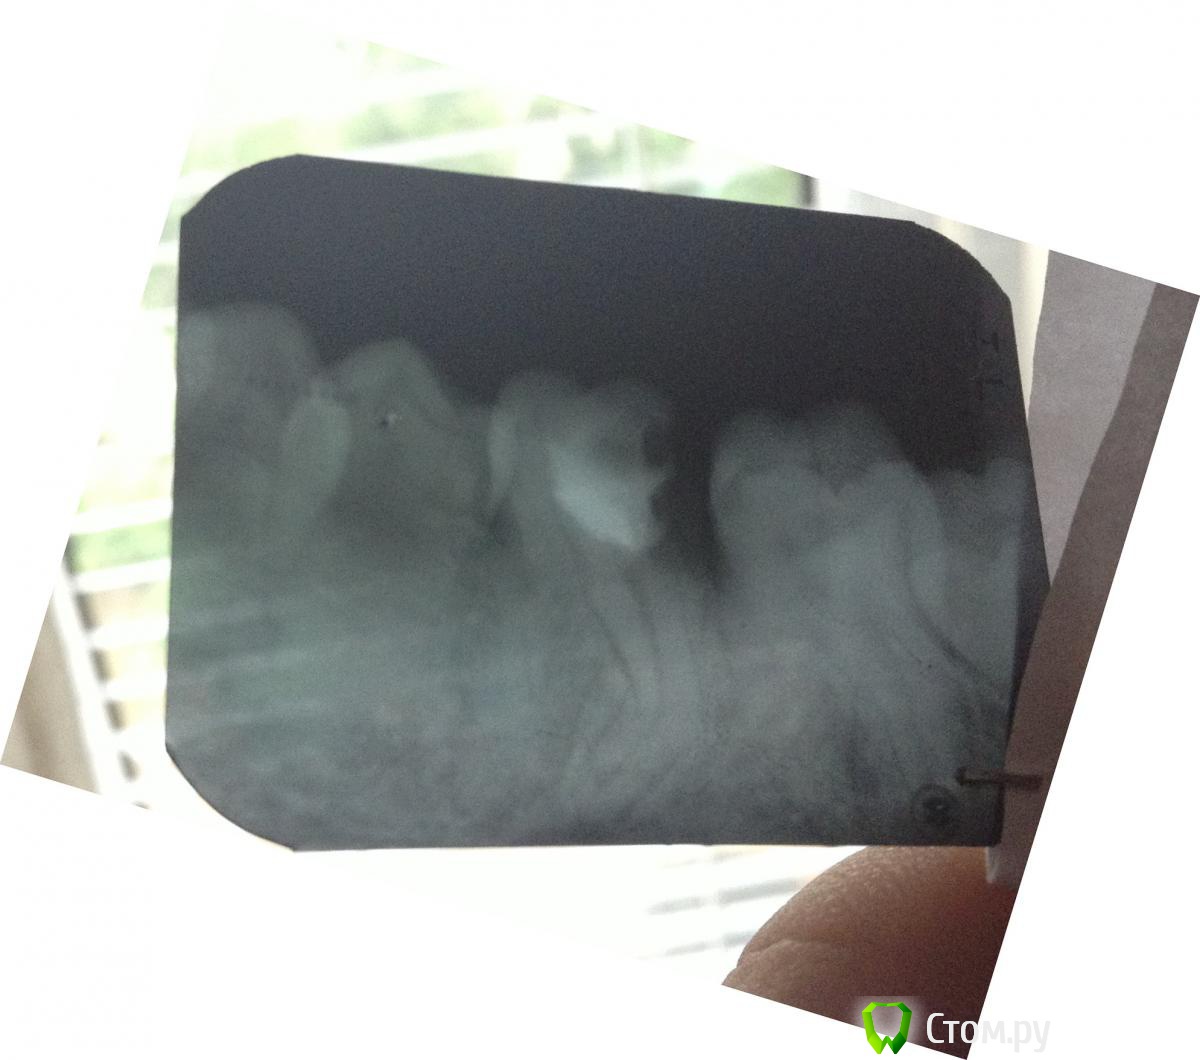

and13 Опубликовано 3 июня, 2014 Автор Поделиться Опубликовано 3 июня, 2014 сделал еще один снимок. четко видно корни врач говорит что очень сложное тут удаление, корни все кривые. она так же предложила залить каналы спец веществом-лекарством, все это дело запломбировать и оставить так. говорит может года на 3 хватит что думаете по этому поводу? Ссылка на комментарий

IvanK Опубликовано 3 июня, 2014 Поделиться Опубликовано 3 июня, 2014 Ищите Врача, для которого не сложно 1 Ссылка на комментарий

faity Опубликовано 3 июня, 2014 Поделиться Опубликовано 3 июня, 2014 в удалении этого зуба нет ничего сложного, восьмерка сложнее удаляться будет скорее всего. сохранять не стоит, за 3 года уйдет кость и имплантация с аугментацией выйдет минимум в 2 раза дороже, чем просто имплант сейчас Ссылка на комментарий